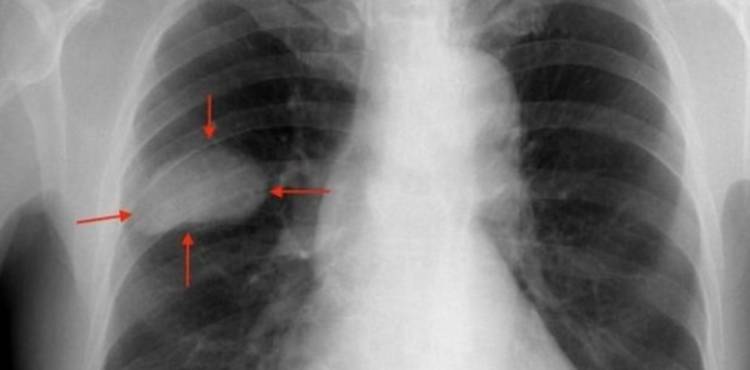

Un cáncer de pulmón avanzado visto a través de Rayos X. La sobrevida es cada vez mayor. Imagen: ½. Se trata del amivantamab, que fue aprobado por la Anmat y se utiliza en casos avanzados. Advierten sobre la importancia de ampliar los testeos genéticos en los diagnósticos.